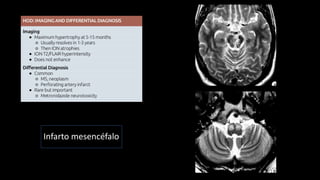

Degeneração Walleriana

• Lesão aguda

• Realce

• Restrição

• Lesão aguda •Realce • Restrição